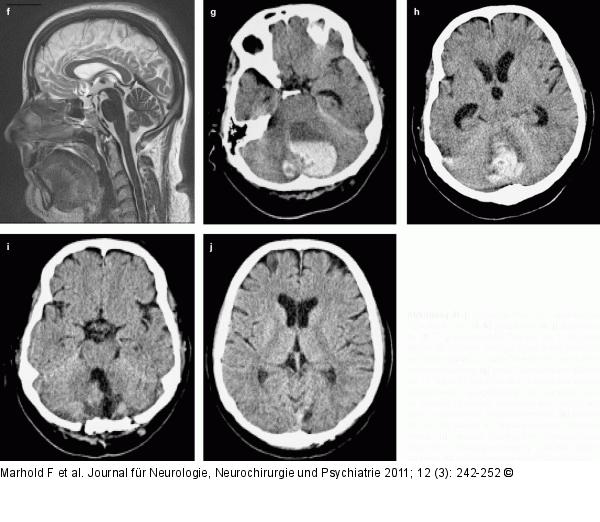

Abbildung 4f-j: PICA-Insult 38-jährige Frau mit eingeblutetem PICA-Insult links: (f–h) präoperativ, (i, j) postoperativ, (f) T2-gewichtete MRT-Sequenz am 2. Tag nach Beginn der Ischämie: fleckiger Insult in den Tonsillen, kein Hydrozephalus, basale Zisternen frei, keine Hirnstammverlagerung, (g) große lateromediane Blutung am 12. Tag mit Einbruch in den hinteren und unteren Kleinhirnwurm, Spiegelbildung des Hämatoms, vierter Ventrikel obliteriert, Hirnstamm nach ventral verlagert, aufstauendes Temporalhorn links, (h) Blutung am 12. Tag median im Oberwurmbereich, Hydrozephalus, (i) mediane subokzipitale osteoplastische Trepanation, Blutungsentleerung, partielle Nekrosektomie, (j) kein supratentorieller Hydrozephalus. |

Abbildung 4f-j: PICA-Insult

38-jährige Frau mit eingeblutetem PICA-Insult links: (f–h) präoperativ, (i, j) postoperativ, (f) T2-gewichtete MRT-Sequenz am 2. Tag nach Beginn der Ischämie: fleckiger Insult in den Tonsillen, kein Hydrozephalus, basale Zisternen frei, keine Hirnstammverlagerung, (g) große lateromediane Blutung am 12. Tag mit Einbruch in den hinteren und unteren Kleinhirnwurm, Spiegelbildung des Hämatoms, vierter Ventrikel obliteriert, Hirnstamm nach ventral verlagert, aufstauendes Temporalhorn links, (h) Blutung am 12. Tag median im Oberwurmbereich, Hydrozephalus, (i) mediane subokzipitale osteoplastische Trepanation, Blutungsentleerung, partielle Nekrosektomie, (j) kein supratentorieller Hydrozephalus. |